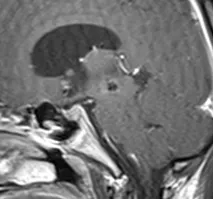

术前MRI

20岁大学生,情况非常危急,来到巴教授所在医院时基本昏迷,很大的中脑海绵状血管瘤出血,而且出现脑积水。